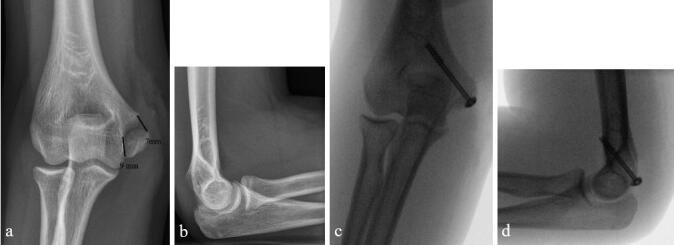

Background and purpose - Controversy exists regarding the optimal treatment for displaced medial epicondyle fractures. We compared the results of nonoperative and operative treatment and calculated the incidence of medial epicondyle fractures in the pediatric census population.Patients and methods - 112 children under 16 years old who sustained > 2 mm displaced fracture of the medial epicondyle were treated in our institution between 2014 and 2019. 80/83 patients with 81 non-incarcerated fractures were available for minimum 1-year follow-up. 41 fractures were treated with immobilization only, 40 by open reduction and internal fixation, according to the preference of the attending surgeon. Outcome was assessed at mean 2.6 years (1-6) from injury with different patient-reported outcome measures. Elbow stability, range of motion, grip strength, and distal sensation were registered in 74/80 patients. Incidence was calculated for 7- to 15-year-olds.Results - Nonoperatively treated children had less pain according to the PedsQL Pediatric Pain Questionnaire (3 vs. 15, p = 0.01) with better cosmetic outcome (VAS 95 vs. 87, p = 0.007). There was no statistically significant difference between the groups in respect of QuickDASH, PedsQL generic core scale, Mayo Elbow Performance Score, grip strength, carrying angle, elbow stability, or range of motion (p > 0.05). All 41 nonoperatively treated children returned to pre-injury sports; of the surgically treated 6/40 had to down-scale their sporting activities. The incidence of displaced (> 2 mm) fractures of the medial epicondyle in children aged 7-15 years was ≥ 3:100,000.Interpretation - Displaced fractures of the medial humeral epicondyle in children heal well with 3-4 weeks' immobilization. Open reduction and screw fixation does not improve outcome.

患者与方法-2014 年至 2019 年,我们机构收治了 112 名 16 岁以下、伴有>2mm 内侧髁突移位骨折的儿童。83 例患者中的 80 例(81 例未嵌顿骨折)获得了至少 1 年的随访。根据主管医生的偏好,41 例采用单纯固定,40 例采用切开复位内固定治疗。采用不同的患者报告结局测量方法评估平均 2.6 年(1-6 年)的结果。在 74/80 例患者中记录了肘部稳定性、活动范围、握力和远端感觉。计算了 7-15 岁儿童的发生率。